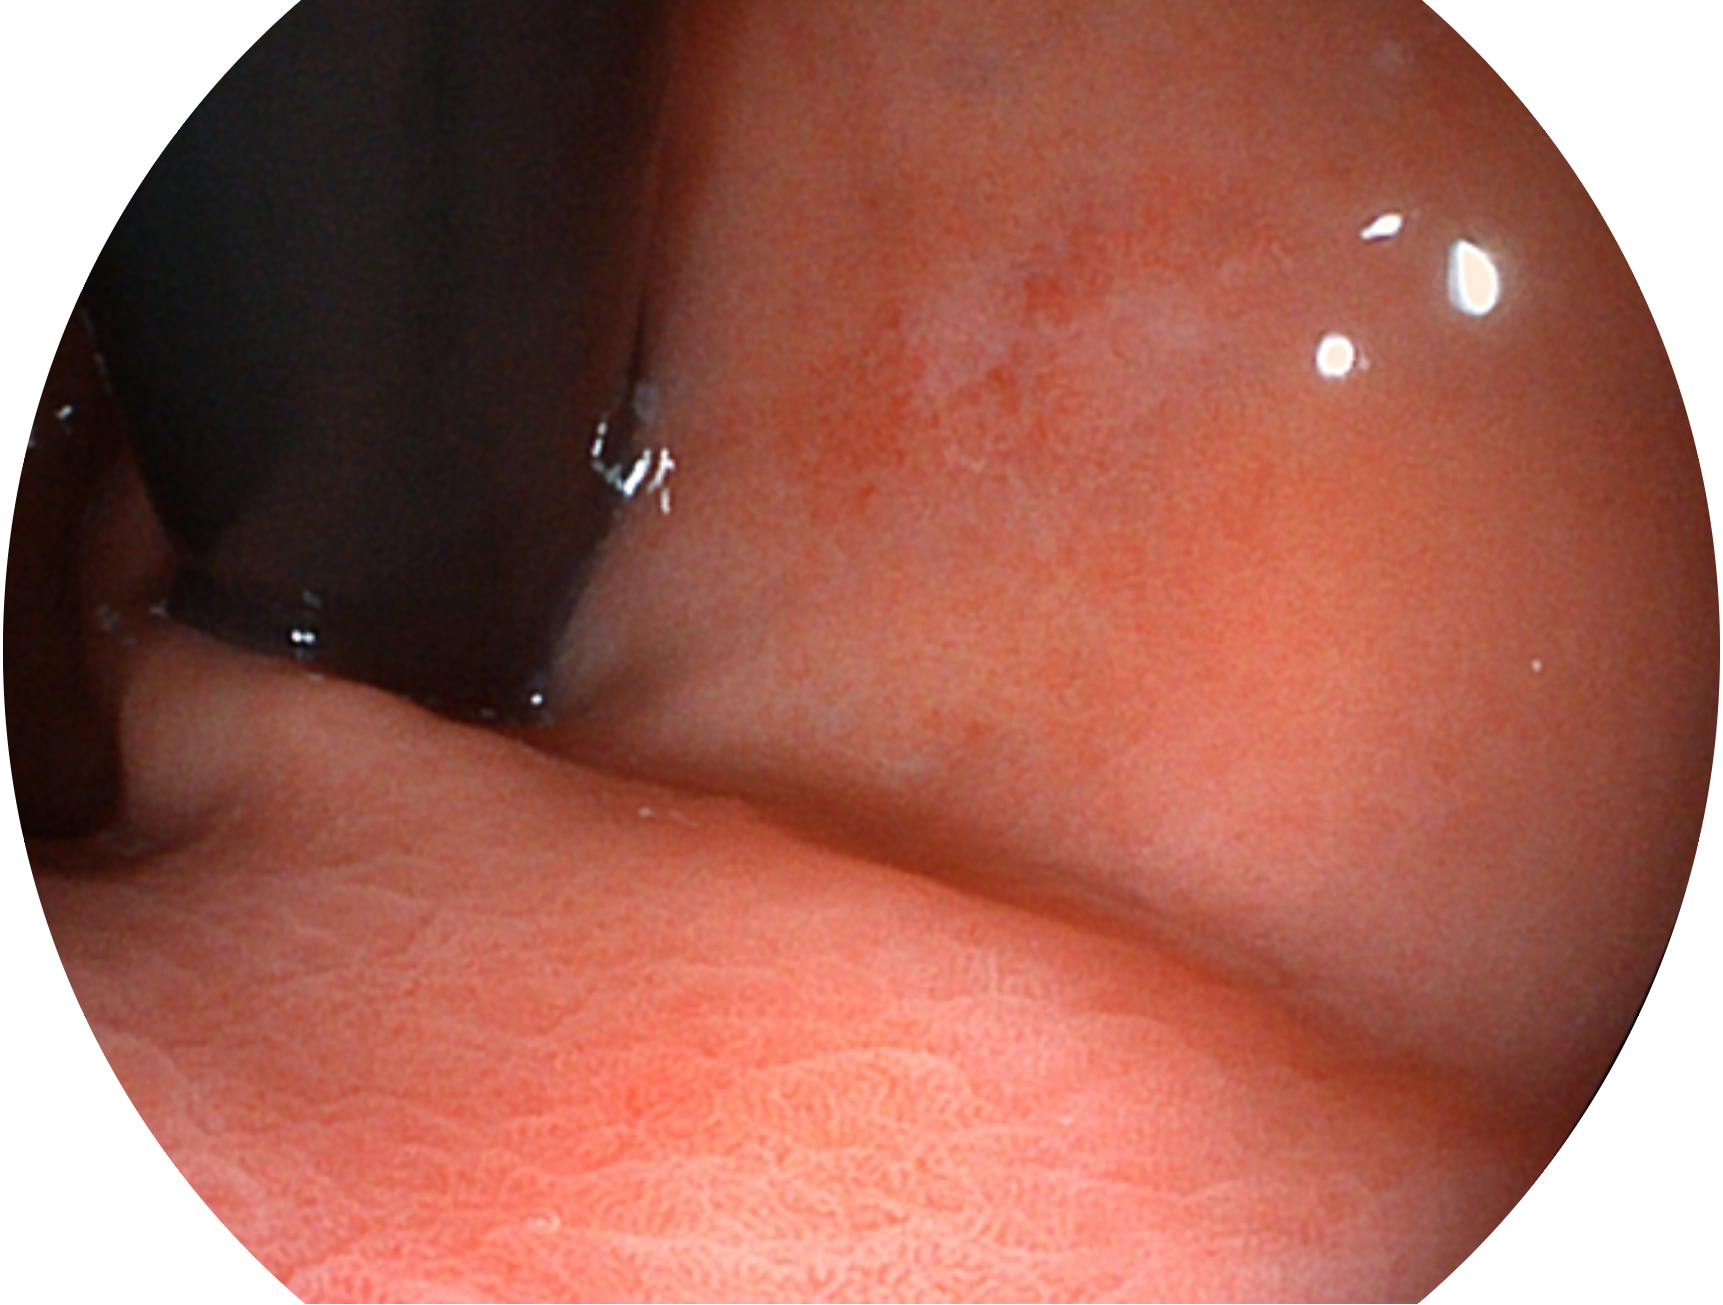

• 白光图像 VIST图像

与上一代VIST相比,摒弃了滤光转轮而直接采用光谱组合的方案,加入了血红蛋白吸收高峰与次高峰的蓝紫光和绿光光谱,更有利于黏膜血管吸收,突显浅表层血管和中层血管的对比度,因而具备更高的图像对比度,近景观察时,有助于微细结构变化及病灶边界的观察。